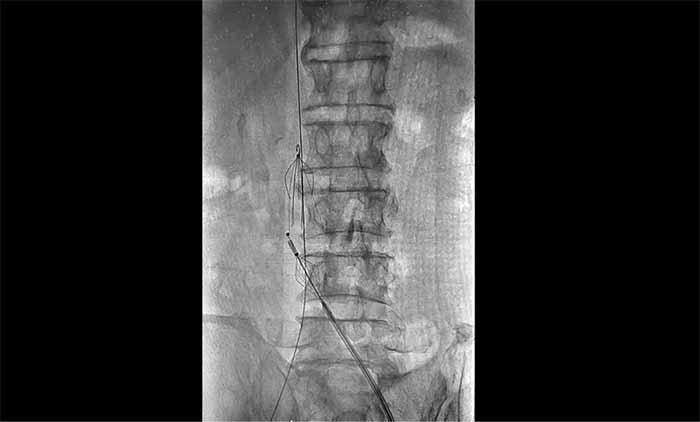

近日,上海蓝十字脑科医院脑血管病科收治了一名脑出血术后长期卧床导致下肢深静脉血栓形成的老年男性患者。患者在外院康复期间发现右下肢严重肿胀,超声提示深静脉血栓,紧急转入本院。

席刚明教授与脑血管病一科4A病区副主任王贵平博士分析指出,下肢深静脉血栓一旦脱落,可随血流引发肺栓塞,危及生命。考虑到患者血栓形成时间较长、抗凝效果不佳,团队决定行介入手术治疗。术后造影显示血栓基本消失,下肢静脉恢复通畅,患者右下肢肿胀明显缓解。

席教授提醒,即便置入滤器,仍需规范抗凝治疗,以预防新血栓形成并降低脱落风险。